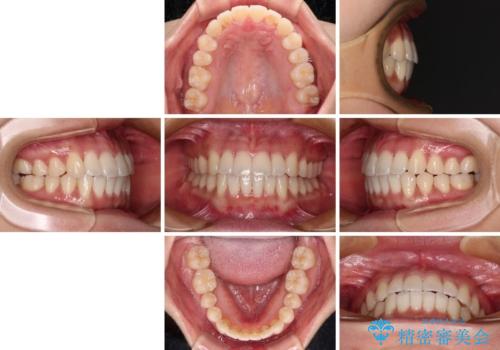

捻れた前歯をできるだけ短期間で 表側のワイヤー矯正

- 1年6ヶ月

日々前歯の捻れが解消されていくので、歯の動きを楽しみながら矯正治療を進めることができました。